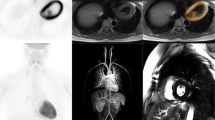

Surgical repair of CHD also often requires prosthetic material, which can be a predisposing factor for infection. In addition to the sternotomy site, multiple sites of infection are possible, including prosthetic conduits, native or prosthetic valves, and cardiac implantable devices. Infectious endocarditis (IE) prevalence is higher in patients with CHD. The reliability of the modified Duke criteria, including echocardiography findings, is limited due to artifacts and complex anatomy. Imaging is critical, not only for diagnosis, but also for the evaluation of response to therapy. The latest guidelines have incorporated 18F-FDG PET/CT findings as a major criterion in the diagnostic algorithms for IE. 18F-FDG PET/CT is also useful for the demonstration of extracardiac complications of endocarditis. Specifically, it allows for the detection of concomitant or alternative infective thoracic foci, such as pericardial collections, mediastinitis, and pulmonary infections (Fig. 21.6). Endocarditis can be associated with septic emboli, with extracardiac foci of infection reported in 15–60% [47,48,49,50,51].

18F-FDG PET/CT of a 10-year-old patient with indwelling central catheter for intravenous hyperalimentation admitted for septic shock. Tricuspid valve endocarditis and lung septic emboli were demonstrated on echocardiogram and chest CT. 18F-FDG PET/CT was requested for the evaluation of left hip pain and performed with myocardial suppression protocol. Selected axial images (a) and Maximum Intensity Projections (b). FDG uptake was noted at the level of the tricuspid valve (long thin arrow). Lung septic emboli were present, some with cavitation (open arrow). Residual activity is seen at the FDG injection site (arrow head). No hip anomaly or other focus of infection was detected. The patient was known for splenomegaly

Ventricular Assist Devices

Infection affects nearly 15–20% of patients within a year of ventricular assist device (VAD) implantation, with infection at the driveline exit site seen most frequently. If isolated, the driveline can be debrided and revised, and the infection treated with antibiotics. Infection extending to internal components is associated with a high mortality rate and needs to be treated more aggressively. 18F-FDG PET/CT has been shown useful in detecting infection of VADs in the adult population, with a pooled sensitivity of 92% and specificity of 83%, resulting in management changes in as much as 80% of patients [55,56,57,58] (Fig. 21.7).

18F-FDG PET/CT was performed in a 1.5-year-old girl with a history of recurrent fever and known Berlin Heart, a left ventricular assist device (LVAD). There was evidence of pneumonia in the left lung base (open arrow). There was physiologic radiotracer distribution associated with arterial cannula in the ascending aorta (long arrow) and atrial cannula in the left ventricle (short arrow), without evidence of material infection

Cardiac Implantable Electronic Device (CIED) infections can present with superficial incisional infection, pocket infection, infection of thoracic leads, and endocarditis. Although less than 1% of all CIED are implanted in children, there are unique characteristics of the devices used in children. For instance, pacemaker stimulation is epicardial in smaller patients or patients with cavopulmonary connections, and the implantation chamber is often tunneled to the left upper abdominal quadrant (Fig. 21.8). Device dependence is more frequent with certain CHD (e.g., atrioventricular discordance), after open heart surgeries performed near the atrioventricular or the sinus node, and after complex heart surgeries, cardiomyopathies, or malignant ventricular arrhythmias. 18F-FDG PET/CT enables diagnosis of infection, assessment of the extracardiac portion of leads, and localization of septic emboli foci. 18F-FDG PET/CT is particularly effective in differentiating superficial tissue infection from deep pocket CIED infections requiring surgical excision (Fig. 21.9). A recent meta-analysis revealed a pooled sensitivity of 96% and pooled specificity of 97% for local pocket infection. Accuracy was slightly lower for lead infection, with a pooled sensitivity of 76% and specificity of 83% [59, 60].

18F-FDG PET/CT of a 9-year-old patient hospitalized for low-grade fever and induration in the epigastric region. The patient had multiple cardiac surgeries for congenital heart disease (double outlet right ventricle) including an epicardial dual chamber pacemaker implantation with implantable pulse generator in the left upper abdominal quadrant for third-degree atrioventricular block. After an inconclusive ultrasound of the latter region, 18F-FDG PET/CT was performed: Maximum Intensity Projections (a) and selected axial images (b). Increased activity was found on both the non–attenuation-corrected (NAC) and CT attenuation-corrected (CTAC) images around the pacemaker casing (open arrow) and along the tunneled wires (long thin arrow). However, there was no supradiaphragmatic extension to the wires (thin short arrow) or to the epicardial leads (arrowhead). The pacemaker was removed and infection was confirmed. After a course of antibiotics with the patient under external pacing, a new pacemaker was installed, with no further complications

18F-FDG PET/CT of a 15-year-old patient status post atrioventricular defect and coarctation of the aorta repair, post epicardial dual chamber pacemaker (ICD) implantation, and artificial mitral valve insertion. ICD replacement with three endovascular leads and one epicardial lead. There was a known superficial infection around the casing in the left hemithorax secondary to Staphylococcus hominis. As leads could not be properly visualized on echocardiogram, 18F-FDG PET/CT with myocardial suppression protocol was performed. An active infectious process was demonstrated around the ICD casing (short thin arrow) and superficial wires (open arrow). No abnormal uptake was found at the level of the mitral valve (arrow head), endocardial leads (curvilinear arrows) or epicardial lead (long thin arrow). The patient underwent pacemaker extraction. After a course of antibiotics under external pacing, a new pacemaker was installed, without further complication

Pericardial disease can be categorized as infectious versus noninfectious, and malignant versus nonmalignant. Etiologies include infectious, neoplastic, autoimmune, metabolic, iatrogenic, and traumatic causes. More often than not, the cause remains elusive [61]. The standard workup for pericarditis includes a thorough history, physical examination and additional investigations such as electrocardiogram, transthoracic echocardiography, and dosage or serum inflammatory biomarkers. 18F-FDG PET/CT can play a role by assessing the activity of the pericardium and/or pericardial effusion (Fig. 21.10). In addition, whole body 18F-FDG PET/CT can identify patterns of uptake suggestive of either infection, collagen vascular disease or neoplasm [62, 63]. Optimal imaging using myocardial suppression protocols should always be used.

18F-FDG PET/CT of a 5-year-old patient with a history of Kawasaki disease who presented with acute chest pain and heart palpitations. An echocardiogram demonstrated a pericardial effusion. 18F-FDG PET/CT was requested to rule out collagen vascular disease as a clinical cause. Axial (a) and sagittal (b) images show significant pericardial effusion (arrow) with mild and diffuse uptake. The remaining study was normal. Biomarkers were negative. The final diagnosis was idiopathic pericarditis, which responded well to steroids